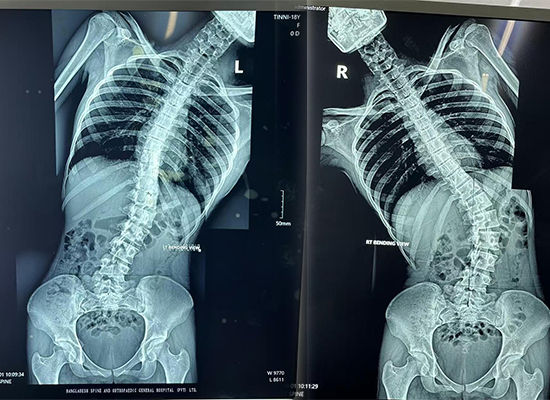

Las imágenes preoperatorias mostraron:

Marcada curvatura lateral de la columna toracolumbar.

Rotación vertebral y prominencia costal.

Hombros desequilibrados y alineación del tronco.

Estos hallazgos confirmaron la necesidad de corrección y fusión de la deformidad de la columna posterior mediante una construcción de varilla y tornillo pedicular..

Radiografía preoperatoria de columna completa que muestra escoliosis toracolumbar en un paciente de 16 años de Dhaka, Bangladesh.